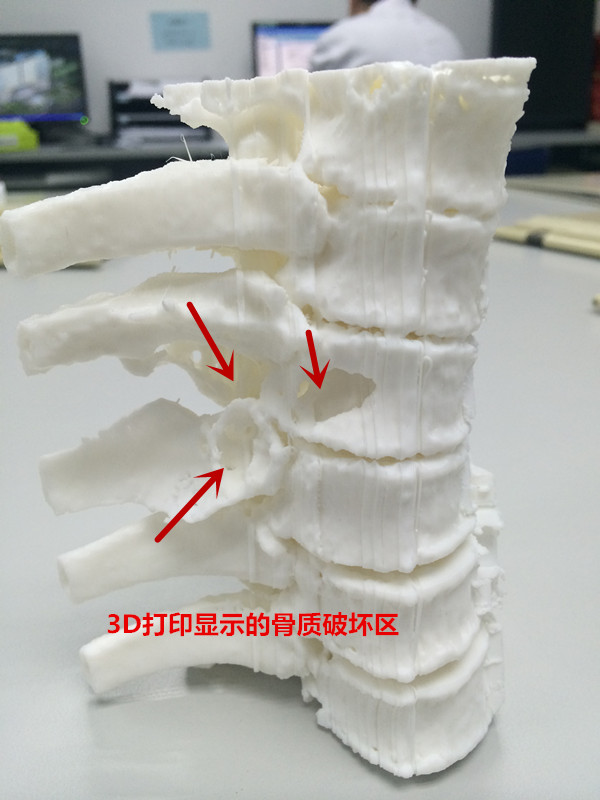

患者入院后,王栋副主任,李锋涛主治医师高度重视,仔细询问患者病情,进行专科查体,分析以往患者的影像学资料,由于肿瘤组织生长巨大,严重压迫右肺,并且已经破坏了胸6椎体及其附件、右侧第6肋骨等,局部结构复杂,为了帮助手术方案的设计,我们采用3D打印技术,术前将肿瘤局部解剖结构打印成3D模型。邀请胸外科张维教授多次会诊,根据3D打印模型制定了详细的手术计划及围手术期治疗方案。经过严密的手术前准备,以王栋副主任、张维教授为主刀、李锋涛主治医师为助手,吴刚副主任医师、罗斌医师为麻醉医师,殷敏、马霞为配合护士,黄亚娟、王芳医师为术中诱发电位监护医师的手术团队努力下,手术顺利完成,成功切除了胸腔内、椎体旁及椎管内肿瘤组织,并进行了脊柱的重建。术后患者恢复良好,很快下肢感觉、肌力恢复,现患者正在康复中。

由于脊柱具有特殊的解剖结构,前方紧邻大血管及内脏,两侧有神经根走行,椎管内是脊髓,这就使得脊柱肿瘤的完整切除变得十分复杂,并且脊柱肿瘤复发后再次手术切除的机会很小,因此脊柱肿瘤手术难度大,复发率高,疗效差,一直是骨肿瘤治疗中的难点。近年来,骨二科先后开展了各种类型的原发性及转移性脊柱肿瘤的手术治疗,尤其是对于单个椎体肿瘤的整体切除,明显减少了术后的复发率,提高了患者的生存时间。对于复杂的脊柱肿瘤,由于局部解剖结构紊乱,使得手术切除变得十分困难,因此我们结合最新的3D打印技术,在术前诊断肿瘤局部进行3D打印,制成模型,在术前根据具体模型设计最佳手术方案及切除范围,术中参考3D模型提高具体操作效率,避免血管神经损伤,明显减少了手术时间及术后并发症,获得了良好的治疗效果。